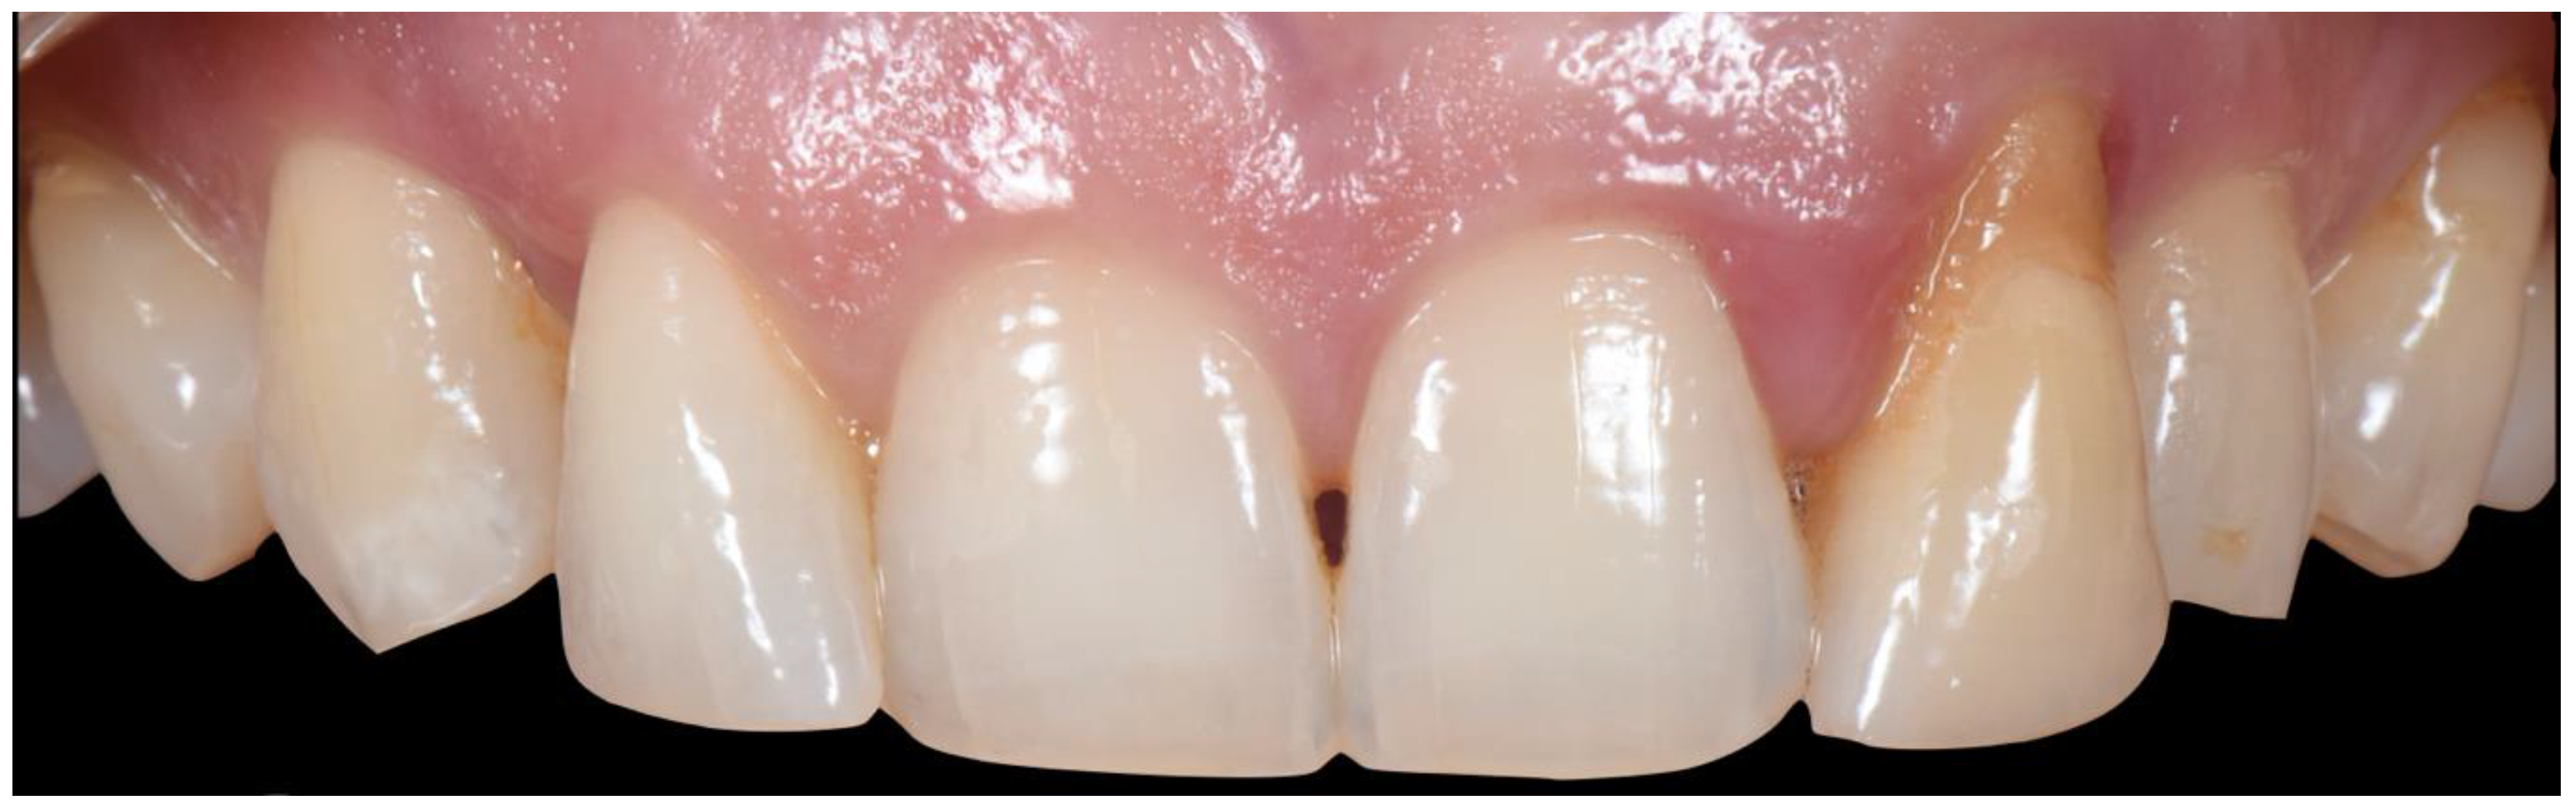

2. Case 1

2.1. “Report and Protocol”

2.2. Pre-Surgical Stage